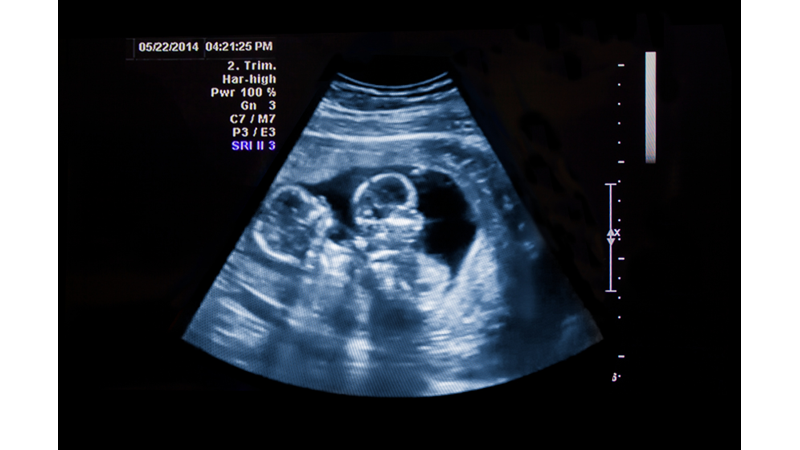

Ana Karnında Simetri

• Daha doğmadan simetri başlıyormuş